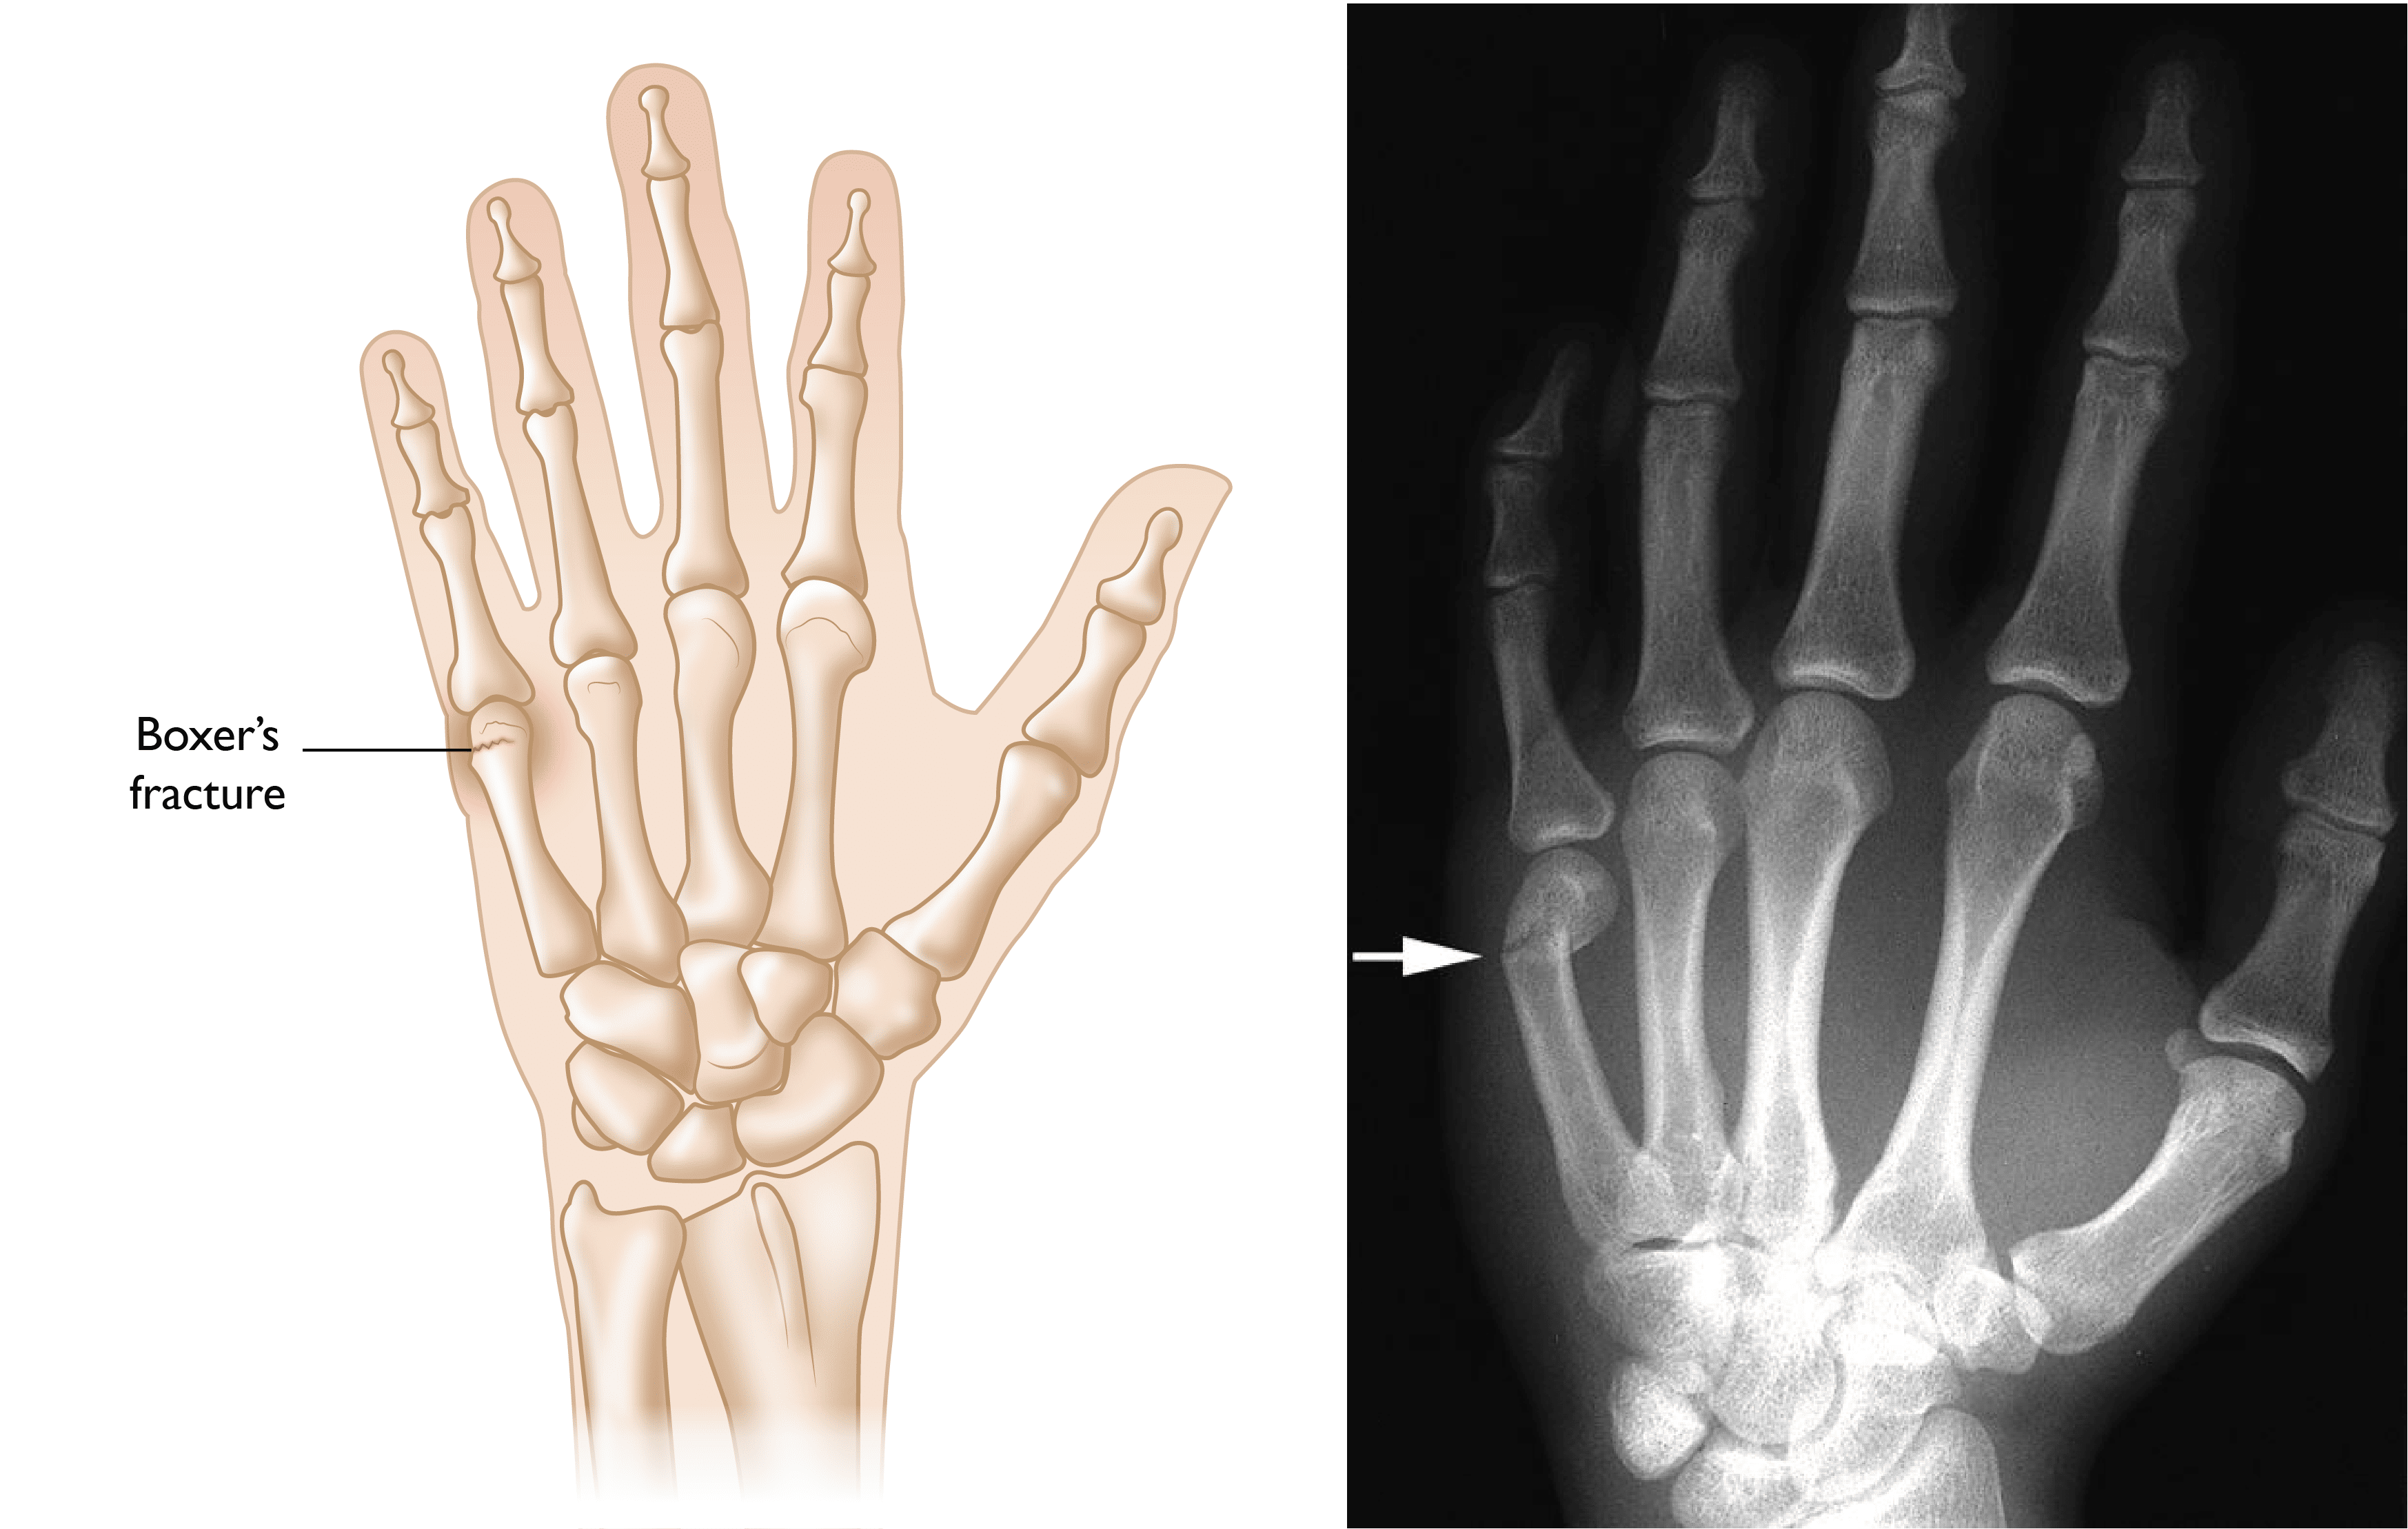

Finger Fractures OrthoInfo AAOS